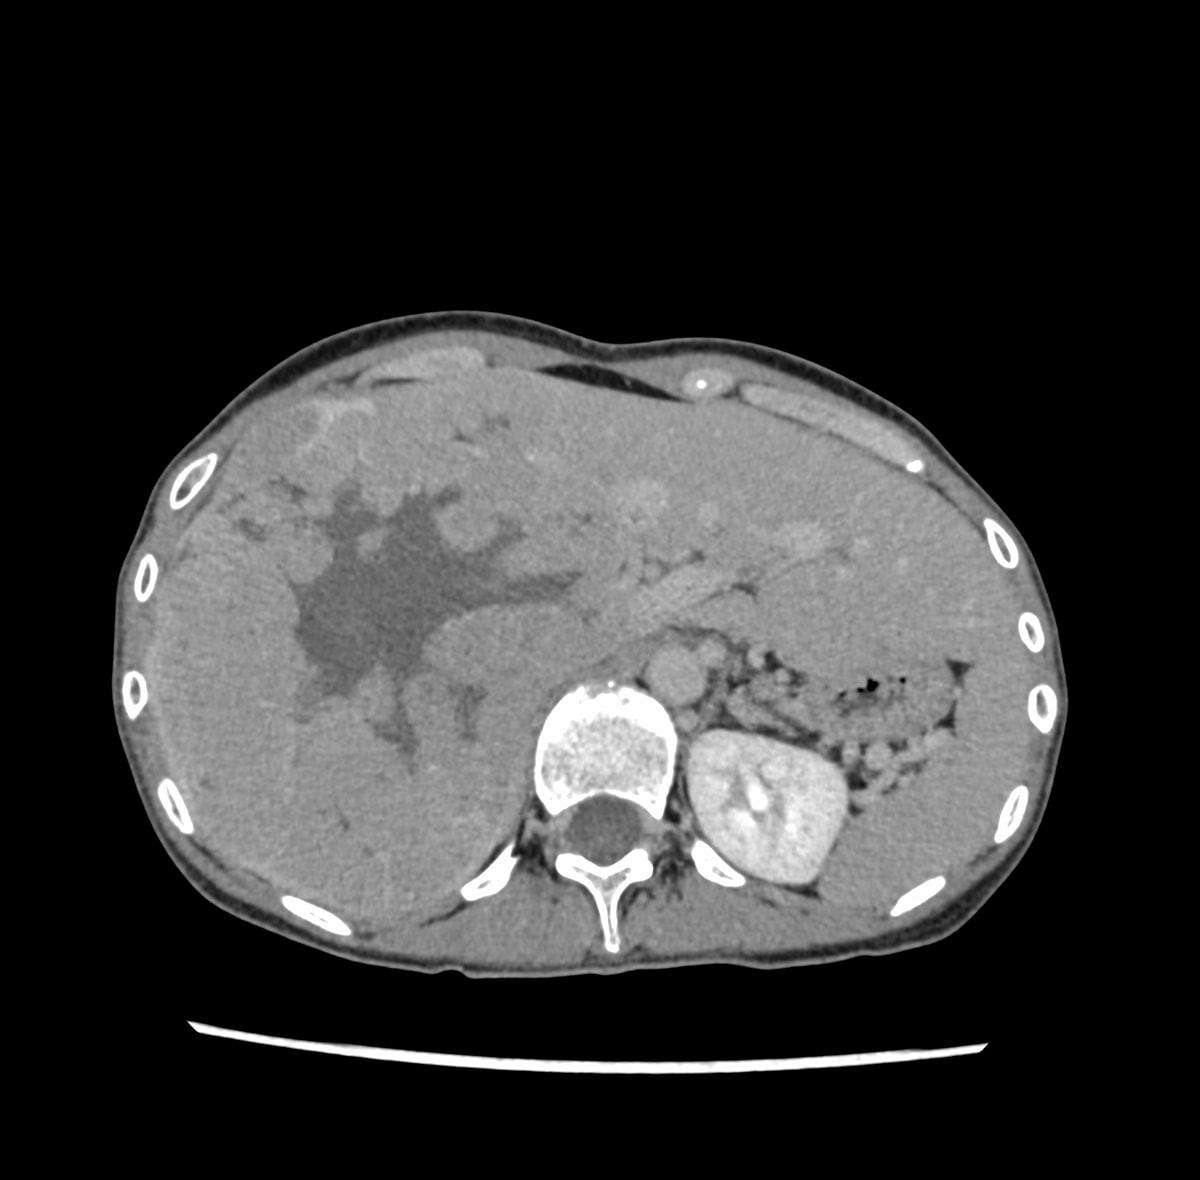

30歳代、女性、38kg、肝細胞癌

右上腹部違和感にて他院を受診し,CTで肝右葉を首座とする巨大肝腫瘍を認め,精査目的に当院紹介.

肝右葉を首座とする24cm大の多結節癒合状の腫瘤性病変を認める.単純CTでは肝実質と等吸収を示し,内部に低吸収域や石灰化を伴っている.造影後早期動脈相から後期動脈相にかけて結節間でやや不均一な早期造影効果を認め,肝静脈相以降では肝実質より相対的に低吸収を示す.門脈本幹から一次分枝レベルにて明らかな造影欠損を認めない.肝細胞癌が疑われ外科的切除が施行され,高~中分化型肝細胞癌と診断された.